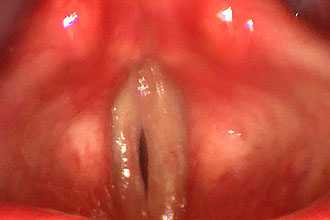

- ларингоскопия - для оценки положения голосовых связок, расстояния между ними, наличия воспалительных процессов или кровоизлияний

Проведение ларингоскопии — внешнего осмотра гортани и дыхательных путей зеркалом.

При необходимости используется ларингоскоп — эндоскопический прибор, позволяющий оценить отёк голосовых связок, скопление слизи, покраснение слизистой оболочки гортани и различные образования [17] [18] .

Для диагностики осматривается гортань. Болезни при ларингоскопии проявляются в виде гиперемии, отека слизистой и утолщения связок. На поверхности отмечаются кусочки мокроты, а в случае гриппозного происхождения ларингита визуализируются кровоизлияния. При лабораторном обследовании регистрируется лейкоцитоз с нейтрофилезом (при бактериальном поражении) или лимфоцитозом - при вирусном инфицировании. Для выявления патогенного возбудителя назначается бактериологическое исследование, материал для которого собирается с поверхности ротоглотки.